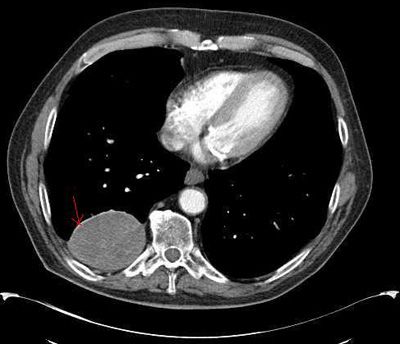

A 76-year-old man presented with left-sided chest pain after a fall. Physical examination found tenderness along the left 8th rib and left basal rales. Chest films showed non-displaced fractures of the 7th and 8th ribs with a small effusion and a right postero-basal rounded opacity (Figure 1). CT scan showed the 8th rib fracture and a prominent pleural-based soft tissue mass in the right lower lobe that measured 7.5 x 5.6 x 9.3 cm (Figure 2). PET scan of the lung revealed minimal metabolic activity in the tumor, a finding consistent with a benign or low-grade neoplasm.

Figure 2.